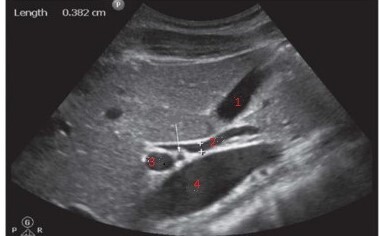

Q

Label the structures

A

1. GB

2. BD

3. MPV

4. IVC

**the arrow points towards the HA